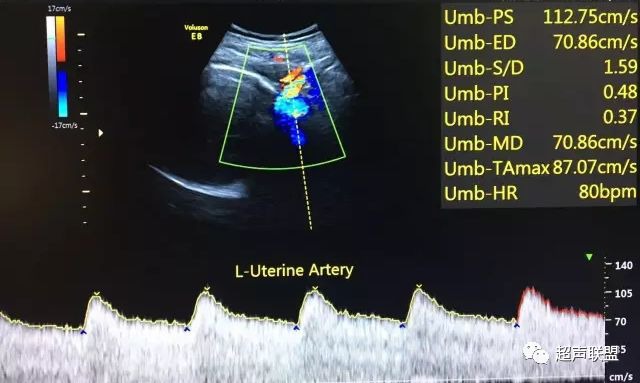

图7 正常中孕期子宫动脉频谱

图8 胎儿宫内缺氧,子宫动脉舒张早期可见切迹